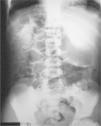

Se realiza Rx abdominal (fig. 1) que se compara con una previa (fig. 2) realizada 4 años antes con ocasión de otro episodio de dolor abdominal; ambas muestran una imagen similar.

La anormal distribución de aire en hemiabdomen derecho con aparente interposición del colon entre hígado y diafragma presente en ambas radiografías, junto con la clínica de dolor abdominal intermitente nos llevó a hacer el diagnóstico de síndrome de Chilaiditi. Su tratamiento conservador, basado en una alimentación equilibrada y rica en fibra, ha evitado nuevos episodios en nuestro paciente.